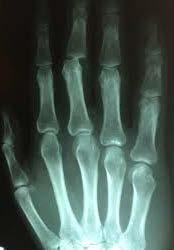

Medicinsk billeddannelse - stiller skarpt på din sygdom og behandling